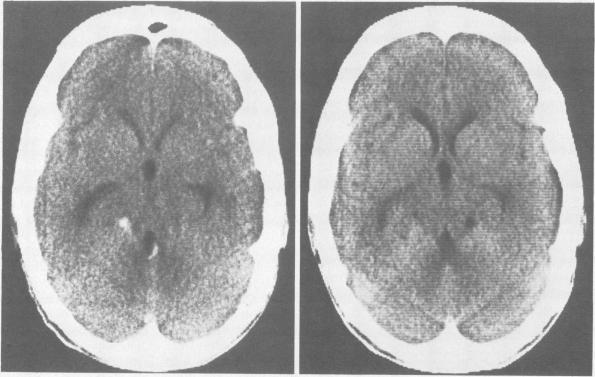

CT-evidence of subarachnoid hemorrhage due to presumed gnathostomiasis.